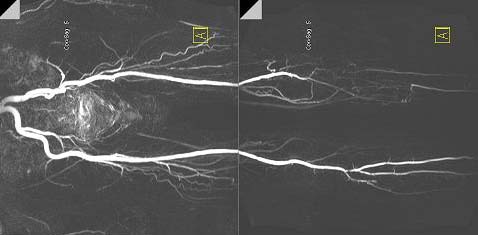

Low leg MRI image1(こちらはS社の非造影シーケンスを用いて描出した症例です。私の以前の研究テーマでした)